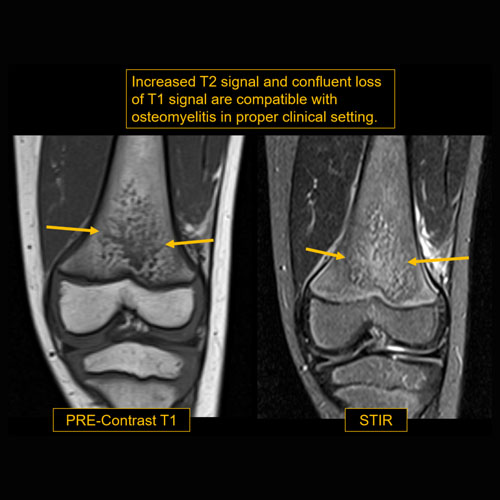

Left toe cellulitis and ulcer. Evaluate for osteomyelitis.Exam

There is periosteal reaction, osseous destruction, or other abnormal marrow to suggest osteomyelitis. |

Yes | NA |

Soft tissue ulcer along the medial/plantar aspect of the great toe.